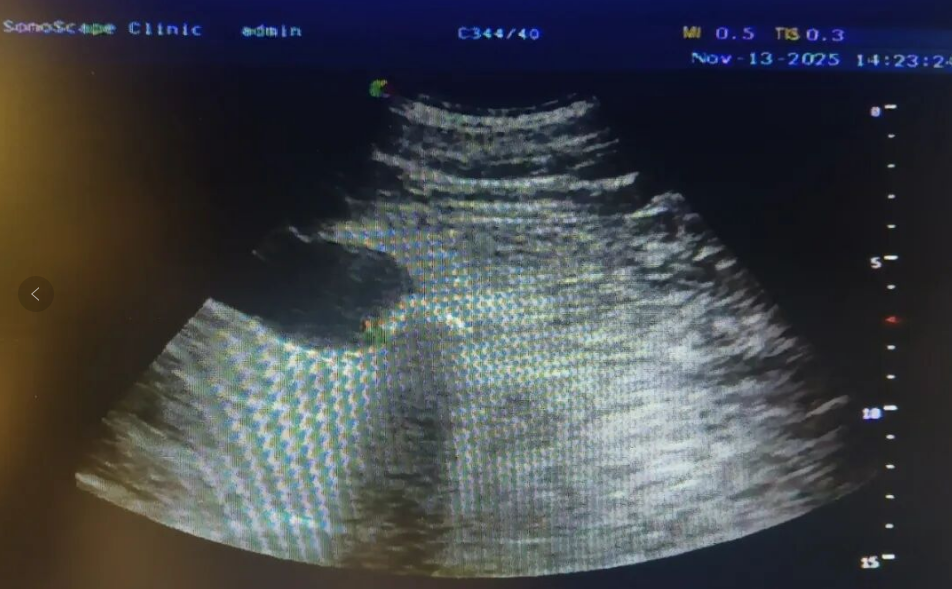

第一次碎石治疗复查,碎石科医生通过精准定位,利用体外冲击波将坚硬的大结石击碎为细长状的小结石群,看到这一结果我们和患者都很欣喜。第二次治疗则针对残留的结石碎片进一步细化,并重点疏通输尿管上段、中段的潜在梗阻点。